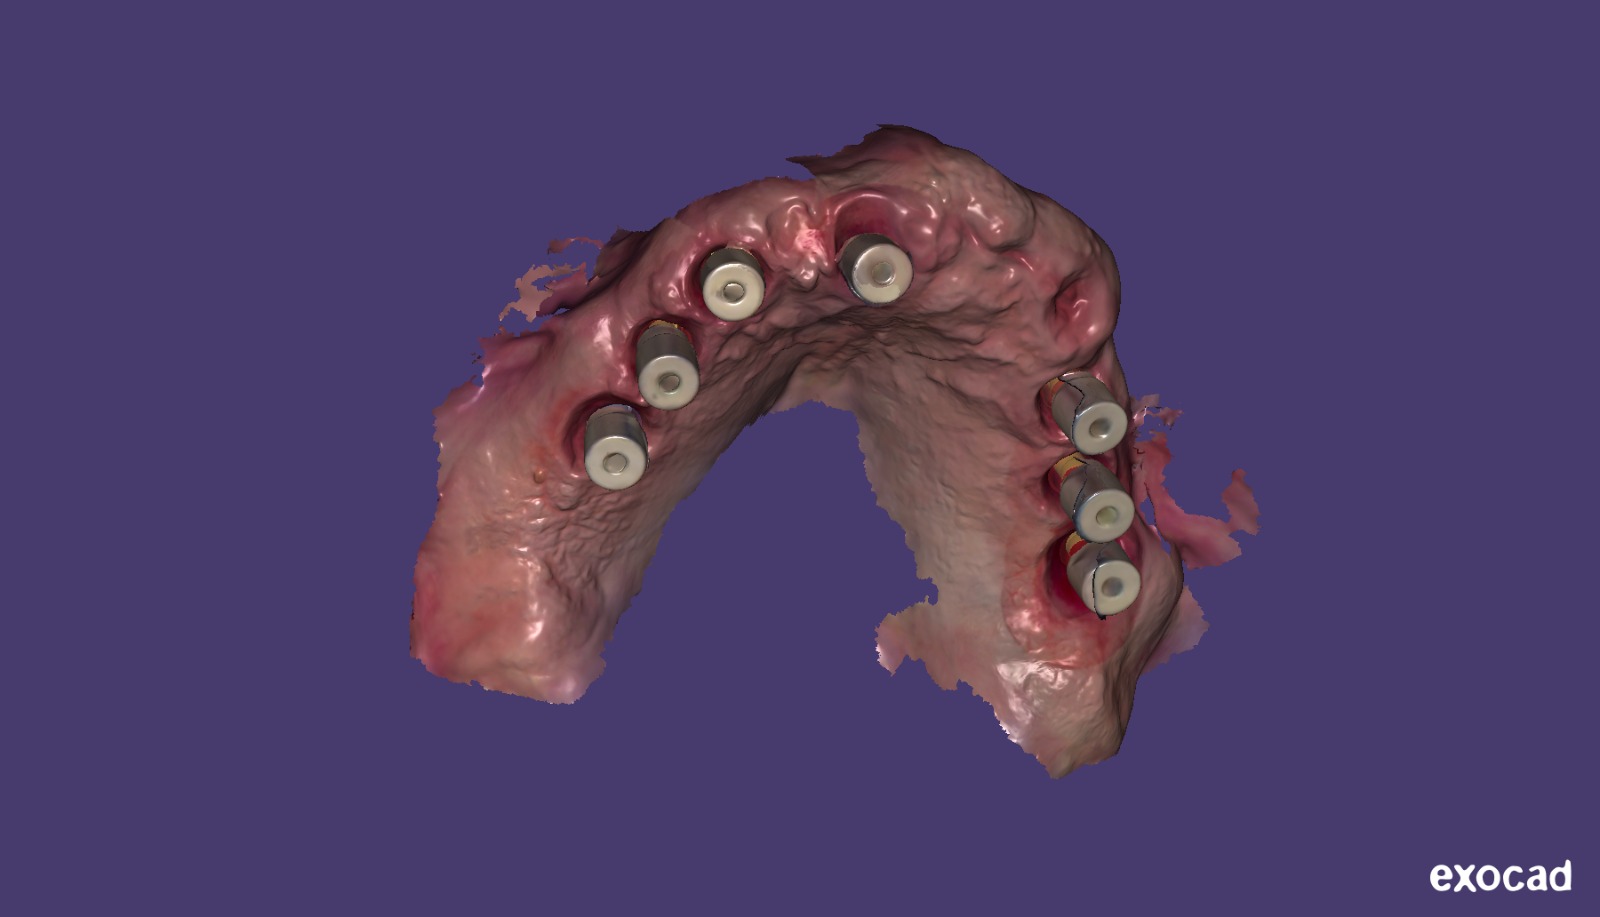

L'importazione delle 3 serie di scansioni intraorali è stata gestita con due software differenti: Exocad (Exocad GmbH - Darmstadt - Germania) e ModelPro (AbutmentCompatibili.com - IPD Dental Group - Barcellona - Spagna) per la parte relativa ai modelli (Fig. 5, 6, 7).

Fig. 6. Scansione intraorale importata in Exocad

Fig. 7. Scansione intraorale importata in ModelPro per la progettazione dei modelli da stampare